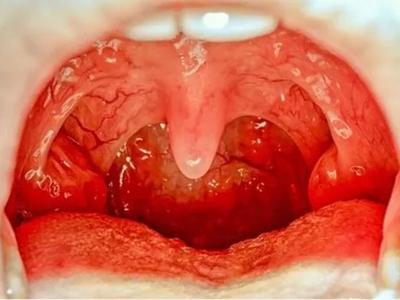

扁桃体

红肿 · 化脓

淋菌性咽炎扁桃体肿大化脓图

淋菌性咽炎双侧扁桃体出现红肿、膨大,由于炎症未得到控制,双侧扁桃体表面形成了好多化脓的黄白色圆块,大小不一,病灶明显高出表面,病情较为严重,应尽快就诊处理。